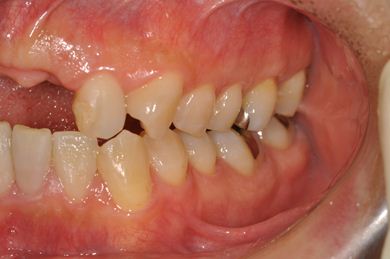

| 性別/年齢 | 男性 / 36歳 | ||||||||||||||||||||||||||||||||

| 主訴 | 事故で欠損した上部の歯4本、下1本のインプラント治療相談。 | ||||||||||||||||||||||||||||||||

| 治療内容 | インプラント2本(GBR、自家骨移植)、メタルボンドセラミック4本、結合組織移植術 | ||||||||||||||||||||||||||||||||